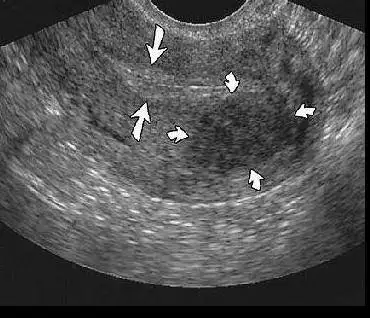

Evet rahim duvarıyla ilgili 3 çizgi sağ sol duvarın eşit ve belirgin şekilde oluşmasıyla oluyor geçen resim paylaşmıştım.zaman zaman olabiliyor kalıcı bir durum değil 3 çizgi olmaması .östrojen dağılımıyla ilgiliKızlar merhabalar son günlerde 3 çizgi olayını görür oldum bu sayfalarda. Rahim kalınlığıyla mı ilgili bu ilk kez duydum?

Yarın bakayım bakalım benımkı nasıl gorunecek1.resim dalgalı yani eşit şekilde kalınlaşmamıs bir tarafı ince bir tarafı kalın

2.3.çizgi oluşmamış fazla kalın rahim duvarı

3.3çizgi oluşmuş transfere uygun duvar

Evet malesef ben acı bı sekilde tanıştım hep okudum öncesinde kalınlık yüzünden iptal onu takmıştım bende ama onda bile bı sistem varmış1.resim dalgalı yani eşit şekilde kalınlaşmamıs bir tarafı ince bir tarafı kalın